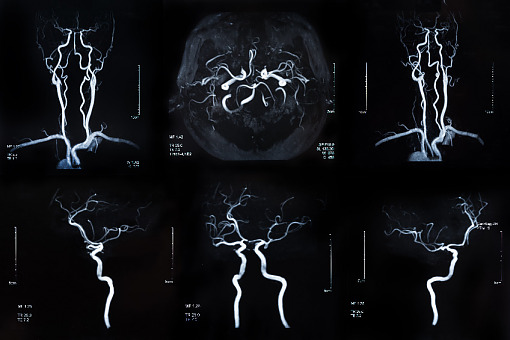

Obecnie w ramach świadczeń gwarantowanych dla pacjentów z tętniakami mózgu dostępnych jest wiele zabiegów, które pozwalają wyłączyć tętniaka z układu krążenia i tym samym zmniejszyć ryzyko wystąpienia groźnych dla życia powikłań. Ale jak wskazuje prezes AOTMiT, oceniane świadczenie, czyli zastosowanie urządzenia do embolizacji typu flow disruptor (EFD, Endosaccular Flow Disruptor), poświęcone jest tętniakom o kształcie workowatym, małej średnicy, szerokiej szyi, zlokalizowanych w rozwidleniach tętnic mózgowych. Te cechy sprawiają, że ich zaopatrzenie w inny sposób jest utrudnione.